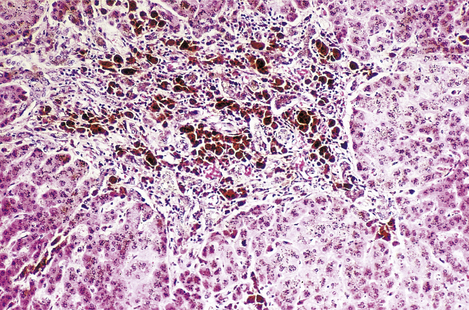

image

Fig. 16.8 Histology of intrahepatic cholestasis in biliary obstruction. The bile canaliculi are stuffed with stagnant brown bile that cannot be discharged from the liver because the common bile duct is blocked by a gallstone. Similar appearances result from viral hepatitis and some adverse drug reactions.

Bile accumulates within the liver, initially in the canaliculi (Fig. 16.8) and later within the intrahepatic bile ducts. Rupture of these may result in extravasation of bile into the adjacent liver tissue; the resulting necrosis has been misnamed as a ‘bile infarct’. The portal tracts are oedematous and infiltrated with neutrophil polymorphs. The hepatocytes at the edge of the portal tract undergo ductular metaplasia. Cholangitis is recognised histologically by the presence of neutrophil polymorphs in the bile ducts.